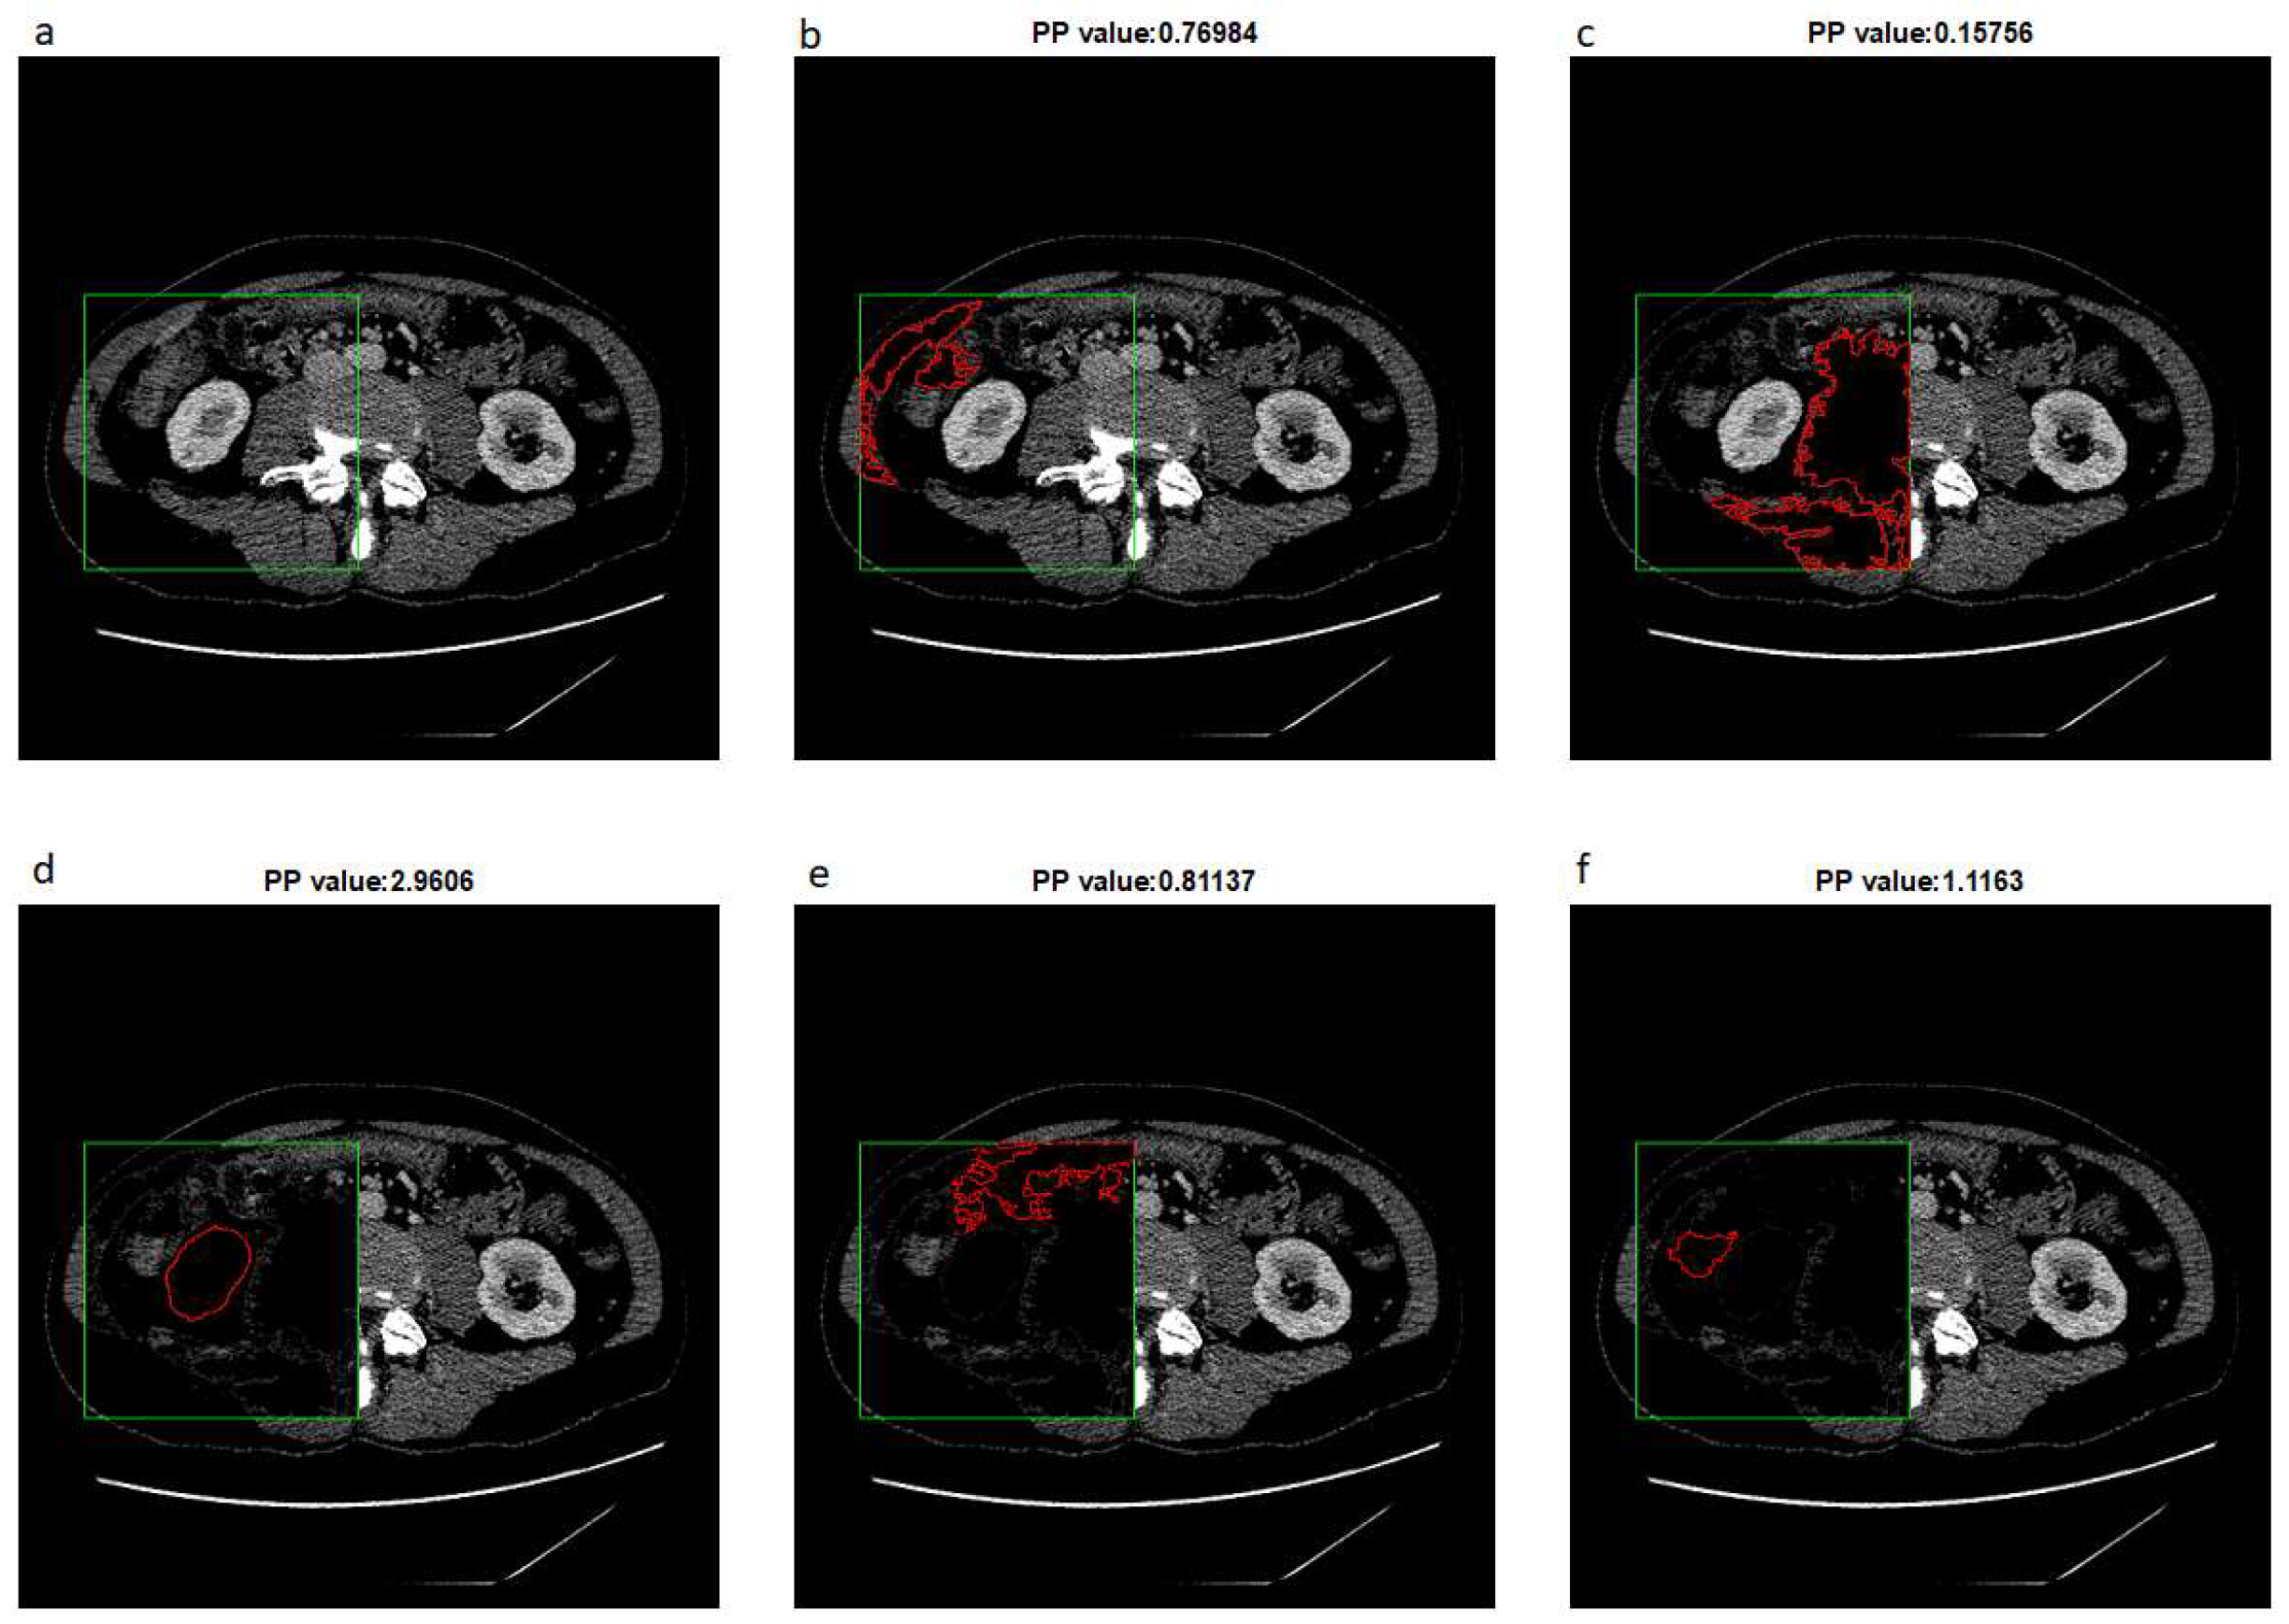

Figure 2 shows the result of the extended-maxima transform operation for selected H parameters. For each value of H, a s u m P value has been calculated. In the given example, we used as S m a square with the upper left corner position (x, y) = (50,175) and a side length of 200 pixels.

The next step is to leave one result for which s u m P is the highest and fill the holes and denote as H 0 the value of H . In the next step, the extended-maxima transform is executed again but in the raw C t s image. Each time algorithm is executed, the circularity coefficient P P is calculated and the result of the operation is removed from the image. According to this procedure, we generate u number of masks which are potential candidates for the final kidney mask. Finally, the mask of the highest P P value is selected. The result of the next five steps is shown in Figure 3.

Figure 2. The result of the extended-maxima transform operation for the selected parameters H = [30, 70, 110, 120, 140, 170]. The green frame shows an exemplary starting area S m .

Figure 3. The result of the next five steps of extended-maxima transforms and result in removing. For example, (a) is an original image, and examples (bf) show different shapes found in the next steps. The result of the operation is removed from the image after each step. The circularity factor P P is calculated for each result.